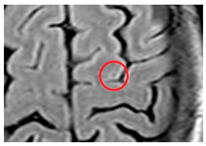

| Lacune: | CSF-filled cavity within the basal ganglia or white matter that is presumed to arise from prior small deep brain infarction [32] | ![]() | 3–15 mm Best distinguished on FLAIR with hypointense centre and hyperintense rim Hyperintense: T2 Hypointense: T1, DWI Isointense: DWI, T2*-GRE |